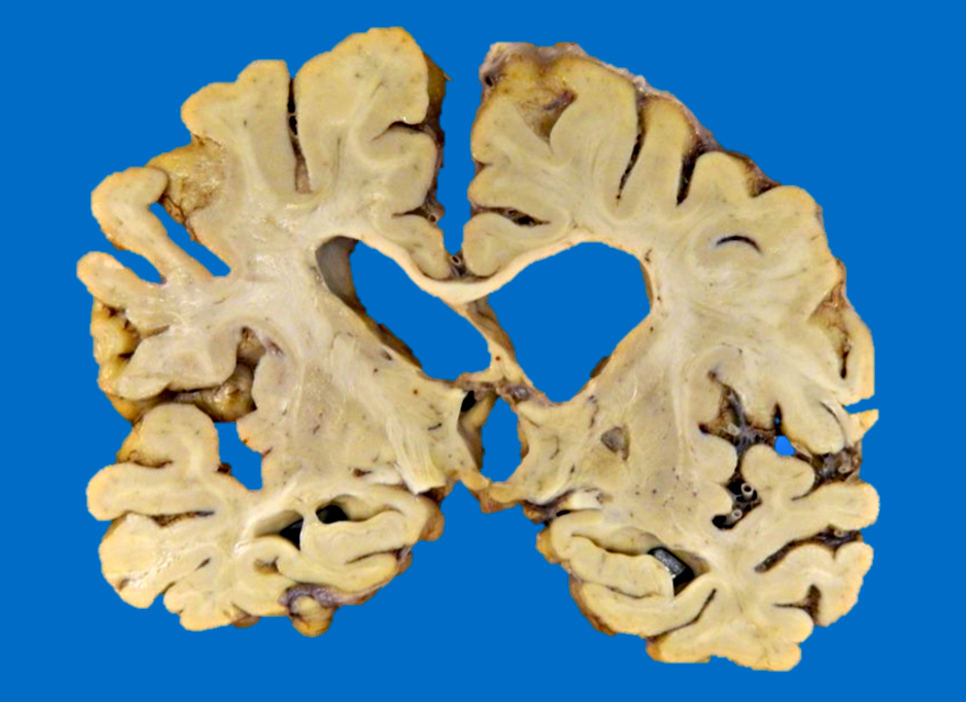

- Chronic (months - years)

- Cavitation (i.e., cystic infarct)

- Thin cortical remnant overlying the cavitation

- In long term survivors of severe global hypoxic ischemic encephalopathy, a markedly thin cortex can be observed due to laminar necrosis

- Lateral ventricle asymmetry can be seen (i.e., ex vacuo ventricular dilation of the affected hemisphere)

- Anterograde loss white matter volume due to an ischemic insult (e.g., atrophy of the ipsilateral cerebral peduncle and pyramid after an MCA infarct with degeneration of the corticospinal tract), ipsilateral brainstem atrophy after extensive supratentorial stroke (corticospinal tract and frontopontine fiber degeneration) and subsequent contralateral cerebellar atrophy due to transsynaptic degeneration (AJNR Am J Neuroradiol 2008;29:354, Eur Radiol 2006;16:592)

- Postinfarct anterograde white matter loss of volume occurs due to Wallerian degeneration or transsynaptic degeneration (AJR Am J Roentgenol 1998;171:813)

- Lacunar infarct: arbitrarily defined as cystic infarcts < 10 mm in length

- Predominantly found at basal ganglia, internal capsule, pons

- Binswanger disease

- White matter structures, including corpus callosum, corona radiata, internal capsule and anterior commissure shows marked loss of volume, discoloration, softening and granular texture predominating in the periventricular areas (Neurology 1995;45:626, J Neurol Sci 2010;299:9)

- Lacunar or large infarcts are frequently observed

- Cerebellar white matter is also commonly affected

- Associated with vascular dementia

Gross images